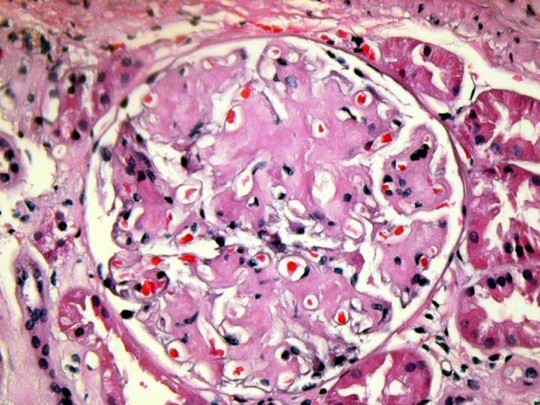

A 56 yo woman with a 25 year history of type II diabetes presents to the clinic. She has required insulin for 20 yrs. Eye exam last year was notable for diabetic retinopathy

On exam, 168/102

UA with 3+ protein, Creatinine 2.6

Based on the histologic specimen below, what is her diagnosis and treatment?

Severe Diabetic Nephropathy:

Most common cause of end stage renal disease in the U.S.

Occurs in both Type I and Type II DM

Histo:

Light microscopy:

- Nodular diffuse nephropathy:

- Acellular, PAS, glycosylated proteins deposited in glomerular tuft

- Start in mesangium and spread to rest of glomerulus, compress capillaries

6 year old boy presents with periorbital edema. Parents report URI two weeks ago.